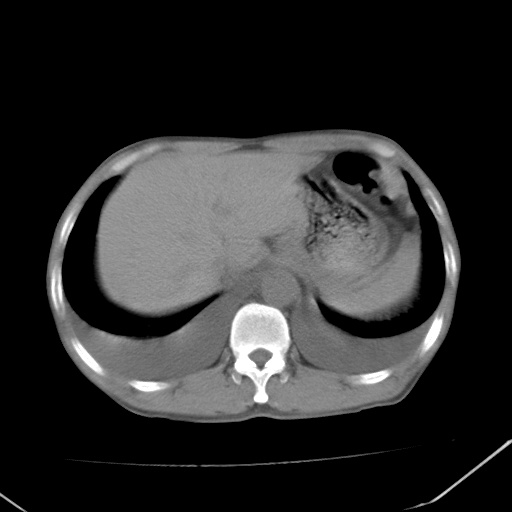

男、42岁、咯血3天。既往有甲亢、贫血、血尿蛋白尿史多年。血象:wbc:6.   中性粒:70.6%。

结合病史考虑双肺泡积血,双侧胸腔少量积液;肺水肿待排(肺水肿症状重)。

双肺堆成磨玻璃影,双测胸腔积液。考虑:肺水肿、间质性肺炎、真菌感染、ards、hiv感染、肺出血。

双肺野对称性磨玻璃影,分布于内中带,双侧胸水,患者有咯血。

双肺野广泛对称性磨玻璃影、实变影,以肺门为中心,主要分布于内中带,符合典型肺泡性肺水肿;伴双侧胸腔少量游离积液。结合患者既往病史且咯血就诊,支持多因素(尿毒症等)所致之肺水肿、肺出血、胸水;影像表现暂不考虑心源性水肿,且症状也不太符。需密切随诊结合临床治疗等进一步明确。

心影增大密度略低,双肺磨玻璃样高密度影及双侧胸腔积液,考虑心功能不全继发双肺肺水肿及双侧胸腔积液。心影密度略低,考虑贫血所致。